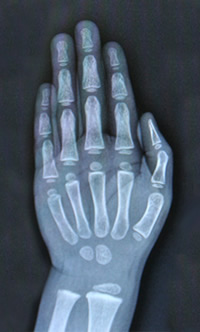

Golisano Children's Hospital / Endocrinology / Pediatric Bone Health Program / Tests & Procedures Tests & Procedures Bone Densitometry X-ray MRI Bone Scan